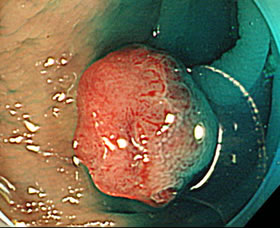

これは、7ミリの浸潤癌です。非常に小さい病変ですが、このような癌化した病変が専門医の通常の検査で見逃されることは極めて稀です。

(もちろん絶対に無いとは断言できませんが、次に述べる「腺腫の見落とし」に比べると、可能性は、はるかに小さいでしょう)